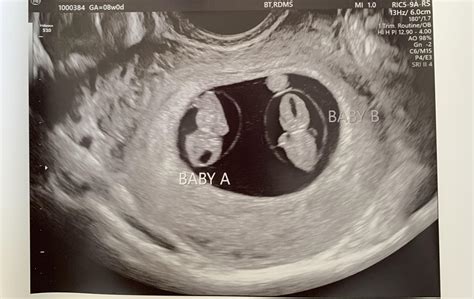

• 9 week ultrasound twins